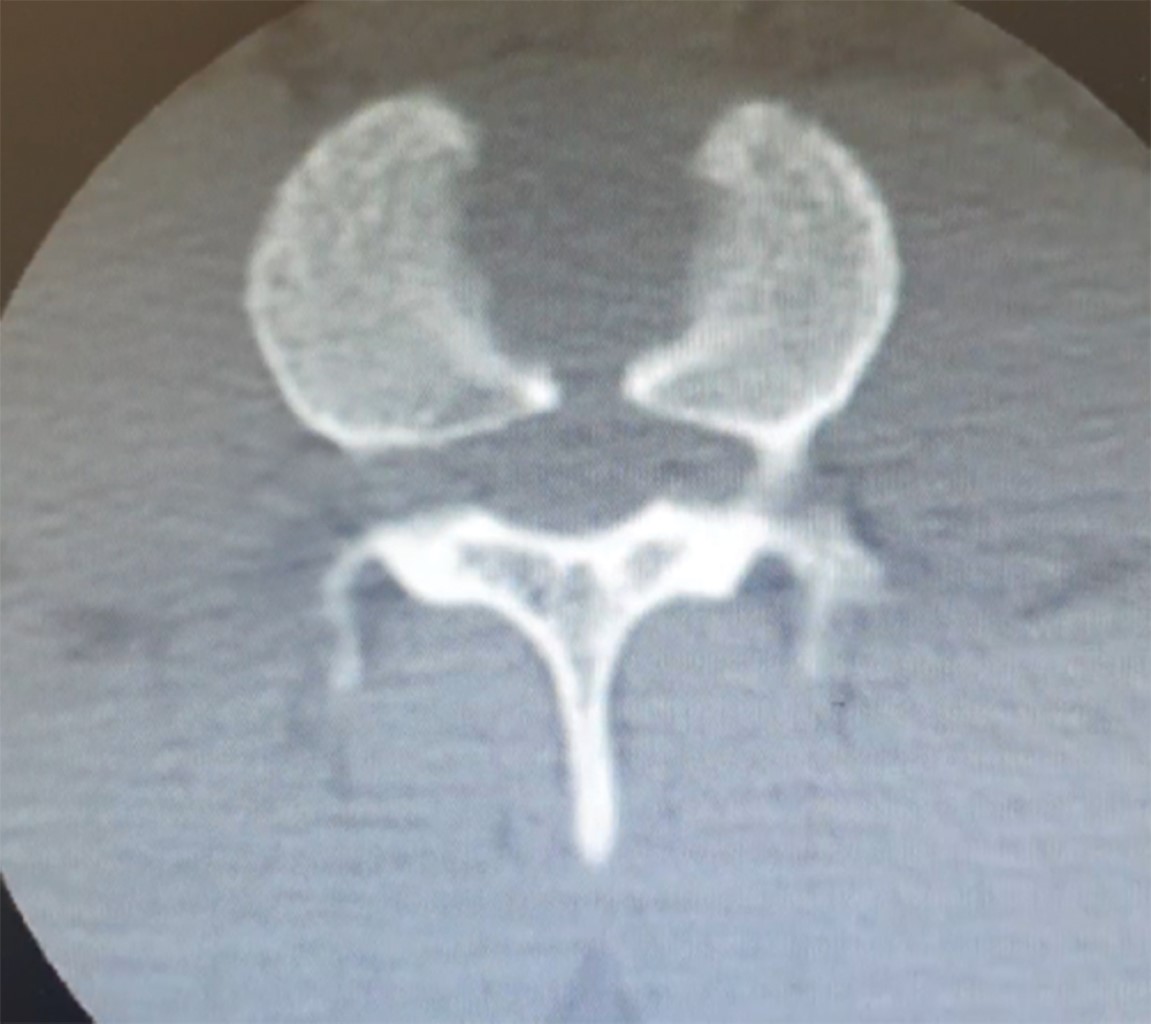

Se realizó tomografía de columna lumbar en cortes sagital, coronal y axial, así como reconstrucción en 3D, donde se identificaron lesiones en alas de mariposa y también se reconoció afectación en cuerpos vertebrales de T5-T6 y T12 (Figuras 3, 4, 5 y 6).